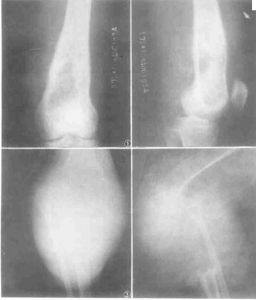

溶骨性侵襲性破壞,軟組織腫塊較明顯,少有骨膜反應和鈣化1、X線檢查 軟組織惡性纖維組織細胞瘤病變表現為密度均勻一致的腫塊,內無鈣化及骨化。骨內惡性纖維組織細胞瘤呈形式多樣的骨破壞:或為大片狀的溶骨性骨破壞,邊緣模糊不清,邊緣有時伴有篩孔樣骨破壞;或為類圓形的單囊、多囊狀骨破壞,周邊有硬化環包繞。本病一般無骨膜反應,皮質破壞者可伴有軟組織腫塊。

本組52例,男33例,女19例;年齡最大75歲,最小12歲,平均年齡48.7歲。病史3個月~5年,平均病史6.8個月。本組中BMFH主要以局部疼痛、腫脹及腫塊為主訴,主要發生於膝關節和肩關節周圍(分別32例和14例,約占88%),股骨近端3例,跟骨、腰椎、髂骨各1例。術前行X線片52例,CT49例,MRI48例。X線及CT以溶骨性骨質破壞為主,常伴有軟組織包塊,MRI清楚的顯示腫瘤侵犯的範圍。

患者,女,52歲,左脛骨BMFH。術前X線片及CT示脛骨斑片樣、蟲蝕狀骨破壞,周圍由硬化邊緣(略) MRI示腫瘤侵犯的範圍、軟組織包塊及周圍比鄰的關係(略)

BMFH由於缺乏特殊的影像學表現,故不能根據術前X線片、CT、MRI明確診斷,但影像學檢查可以幫助診斷,並且對確定手術方案有很大幫助。根據本組資料,作者總結BMFH影像學表現:(1)X線表現:BMFH的X線表現多種多樣,特徵性少。以蟲噬狀、斑片狀或大片狀溶骨性破壞為主,邊界不清,少數可有邊緣硬化,常伴有軟組織腫塊,骨膜反應無或輕微,這是BMFH的重要特點。(2)CT表現:更清楚地顯示骨質破壞和軟組織腫塊,骨質破壞同X線,少數病灶為囊狀或膨脹性,內有粗條索狀及格線狀嵴,並見邊緣硬化,類似良性病變,骨膜反應少見。(3)MRI表現:BMFH的MRI表現缺乏特異性,但其對腫瘤髓內侵犯、周圍邊界可清楚顯示,指導手術切除範圍,還可顯示腫瘤與鄰近血管的關係以及判斷腫瘤術後改變與術後復發等方面優於X線及CT。